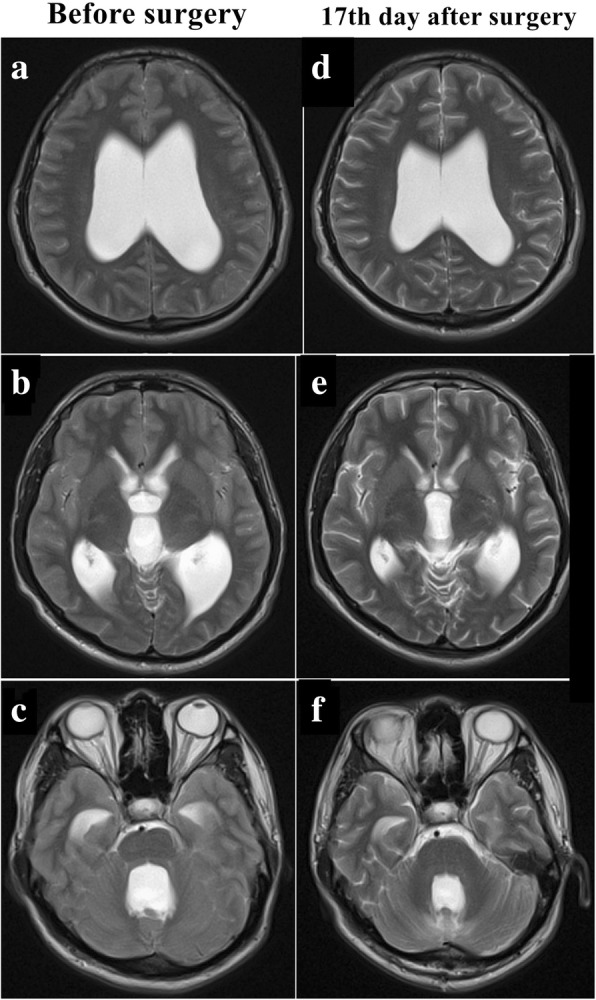

A 24-year-old Han Chinese man presented with a 2-month history of headache and dizziness accompanied by progressive loss of vision in both eyes. His symptoms worsened after a cervical massage 1 week before admission. He had frequent paroxysmal headache associated with nausea, vomiting, and blurred vision. He had a history of mumps and viral encephalitis at the age of 4, which had no sequelae. He had received no past interventions. He had no other medical, family, or psychosocial history. On admission, his visual acuity was 0.5 in both eyes. Physical examination showed bilateral severe optic papilledema, forced head position, and bilateral Babinski’s signs. MRI (Figs. 2 and 3) revealed hydrocephalus with a remarkably enlarged fourth ventricle, crowded posterior fossa, and syringomyelia extending from C1 to C5. His Evans index was 0.4 (61.30/152.9). He underwent a suboccipital and C1 decompression and duraplasty. After the operation, his headache and dizziness were relieved rapidly, and both Babinski’s signs disappeared. On the 17th postoperative day, his visual acuity reached 1.2 in the right eye and 0.6 in the left eye, and his bilateral optic papilledema was reduced. MRI (Figs. 2 and 3) showed that the fourth ventricle had become smaller, the trumpet-like aqueduct had become tubular, and the syringomyelia had dramatically disappeared. His Evans index dropped to 0.36 (55.16/151.96). At his 20th-week follow-up, his visual acuity had reached 1.5 in the right eye and 1.2 in the left eye. At his tenth-month follow-up, his vision in both eyes had reached 1.5, and the volume of the ventricular system had further decreased on MRI. His Evans index had dropped to 0.34 (51.5/149.3). He had no discomfort.

Fig. 2.

Disproportionately large communicating fourth ventricle coexisting with syringomyelia in patient 2. a and d Axial images of the lateral ventricle. b and e Axial images of the third ventricle. c and f Axial images of the fourth ventricle

Both of our patients were DLCFV. Patient 1 presented with a tetraventricular hydrocephalus that returned to normal after shunting the lateral ventricle, which indicated that the aqueduct had been patent or reopened due to the disappearance of the pressure gradient between the supratentorial and infratentorial compartments. Patient 2 presented with not only tetraventricular hydrocephalus but also syringomyelia and crowded posterior fossa, which fulfilled the concept of isolated rhombencephalic ventricle or holoneural canal dilatation proposed by Qi and Abbott [14]. The dramatic regression of patient 2’s clinical and radiological signs shortly after posterior fossa decompression proved the functional obstruction of the outlets, which was in accord with the definition of DLCFV and prompted the role of the crowded posterior fossa in the pathophysiology of DLCFV.

Patient 1 was a typical case of DLCFV without crowded posterior cranial fossa or other abnormality. She was cured successfully with a supratentorial VP shunt. However, the decision-making of the treatment strategy of patient 2 has been a puzzle. He had a crowded posterior fossa and cervical syringomyelia, which could have led to the obstruction of the outflow of CSF from the fourth ventricle. Because it has been proved that the DLCFV is not always responsive to VP shunt and the supratentorial CSF shunt, especially the low-pressure shunt system would increase the risk of upward herniation of the cerebellar tissue. Thus, in view of the obviously crowded posterior fossa and the syringomyelia, the posterior fossa decompression with duraplasty turned into the option of initial management. Although the major cerebellar ptosis could not be considered as a good imaging outcome, patient 2 obtained a good clinical outcome. The effectiveness of posterior fossa decompression to treat postshunt IFV has been reported [3]. Our cases suggested that posterior fossa decompression could be a choice for the initial management of the DLCFV coexisting with crowded posterior cranial fossa or syringomyelia.